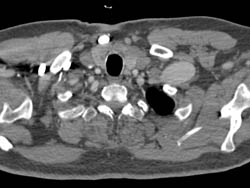

Dilated Sinus of Valsalva